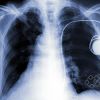

З чого взагалі починається це захворювання? Відповідь — з неконтрольованого ділення клітин у легенях. Всі ми знаємо, що рак легень — дуже тяжка хвороба, яка має серйозні наслідки. Тому надзвичайно важливим є вчасне діагностування лікарями цього захворювання.